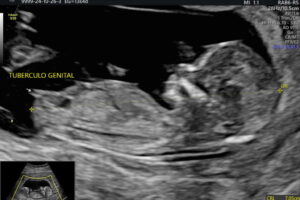

Galería de recuerdos felices Las primeras fotos de Ambar y la historia de sus papás-